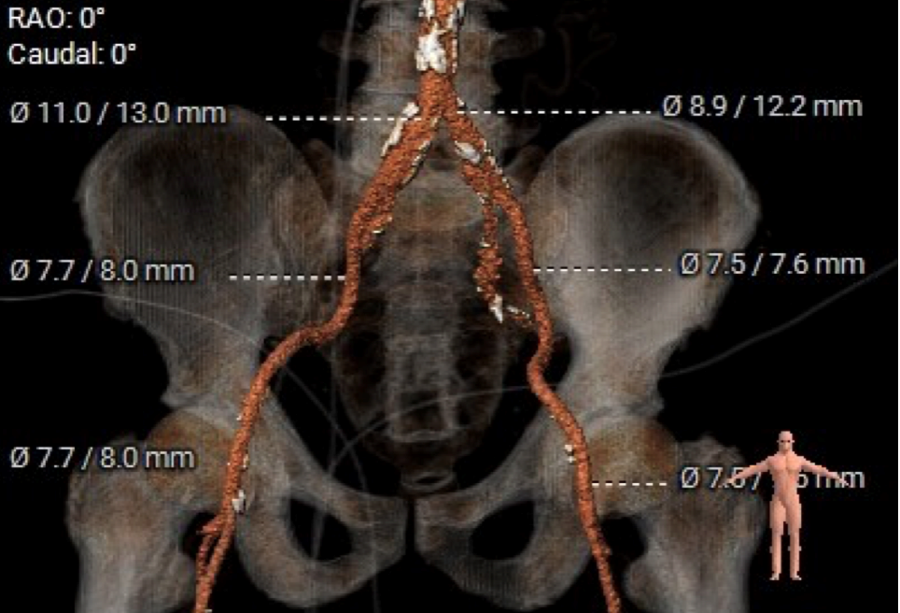

外周血管及主动脉弓解剖

手术过程概览

双侧血管内径良好,所见主动脉血管壁钙化形成

双侧血管内径良好,所见腹主动脉血管壁钙化形成